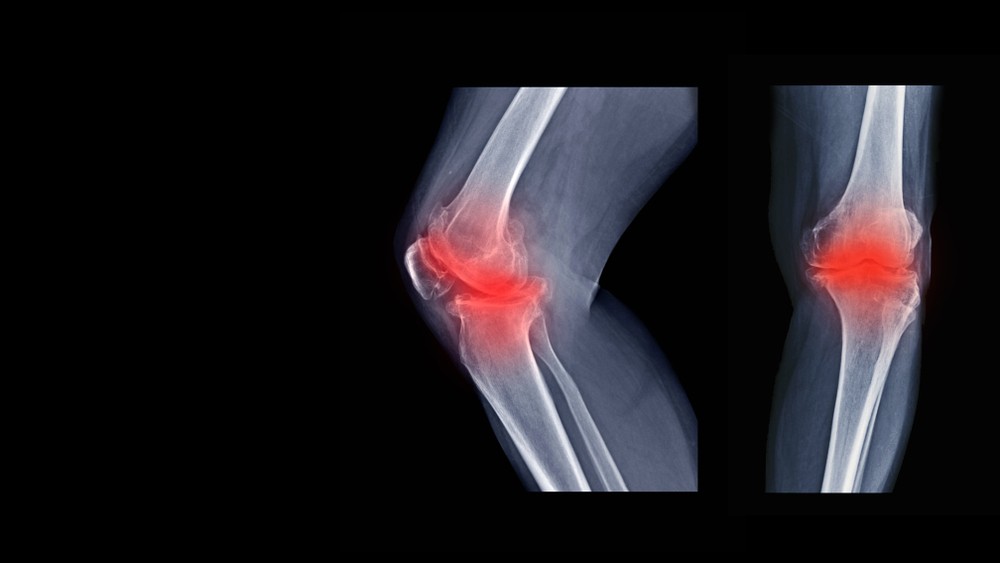

【關節炎】退化性膝關節炎嚴重者連站立都很困難 亂服葡萄糖胺未必有用

隨著中老年人士年齡漸長,加上多年的慢性勞損,容易出現不同類型的關節痛及關節炎。不少人只進食止痛藥作短暫的紓緩,但其實關節痛不可輕視,有可能是患上了退化性膝關節炎,不多加理會的話,日後可能連站立都很困難。

根據本港衞生署資料,關節就是骨頭相連接的地方,方便人體活動。關節發炎可分為急性和慢性。在長者中,最常見的是退化性關節炎,是由於關節慢性勞損而引起,最常受影響的便是膝關節。隨著年月增進,關節液分泌減少。膝關節經長年累月的磨擦而勞損,軟骨變薄。若加上保護關節的肌肉及筋腱疲弱、身體過重、不正確的姿勢和活動,情況便會更差。

最常見的症狀是膝部久不久痛楚,尤其是走動後,特別是下樓梯、擕重物時。間中亦有膝部紅腫發熱。長期患者,或會有關節僵硬,以致關節變形。